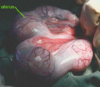

This condition is caused by poor nutrition and is characterized by dilated lymphatics with a jelly-like substance on the outer surface of the heart.

What is the name of this type of atrophy?

Serous atrophy of fat

What is the name of this type of Atrophy?

Serous Atrophy of Fat

Jelly-like material occurs in the middle (arrow) where bone marrow should be.